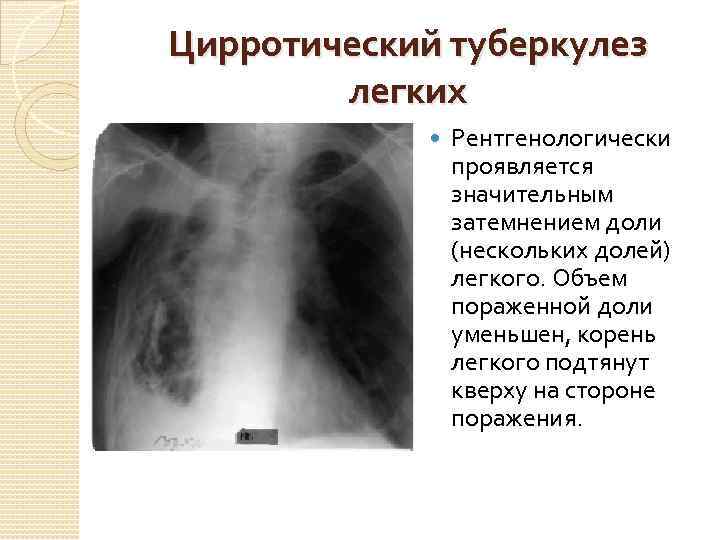

Симптомы и признаки туберкулеза: как распознать заболевание